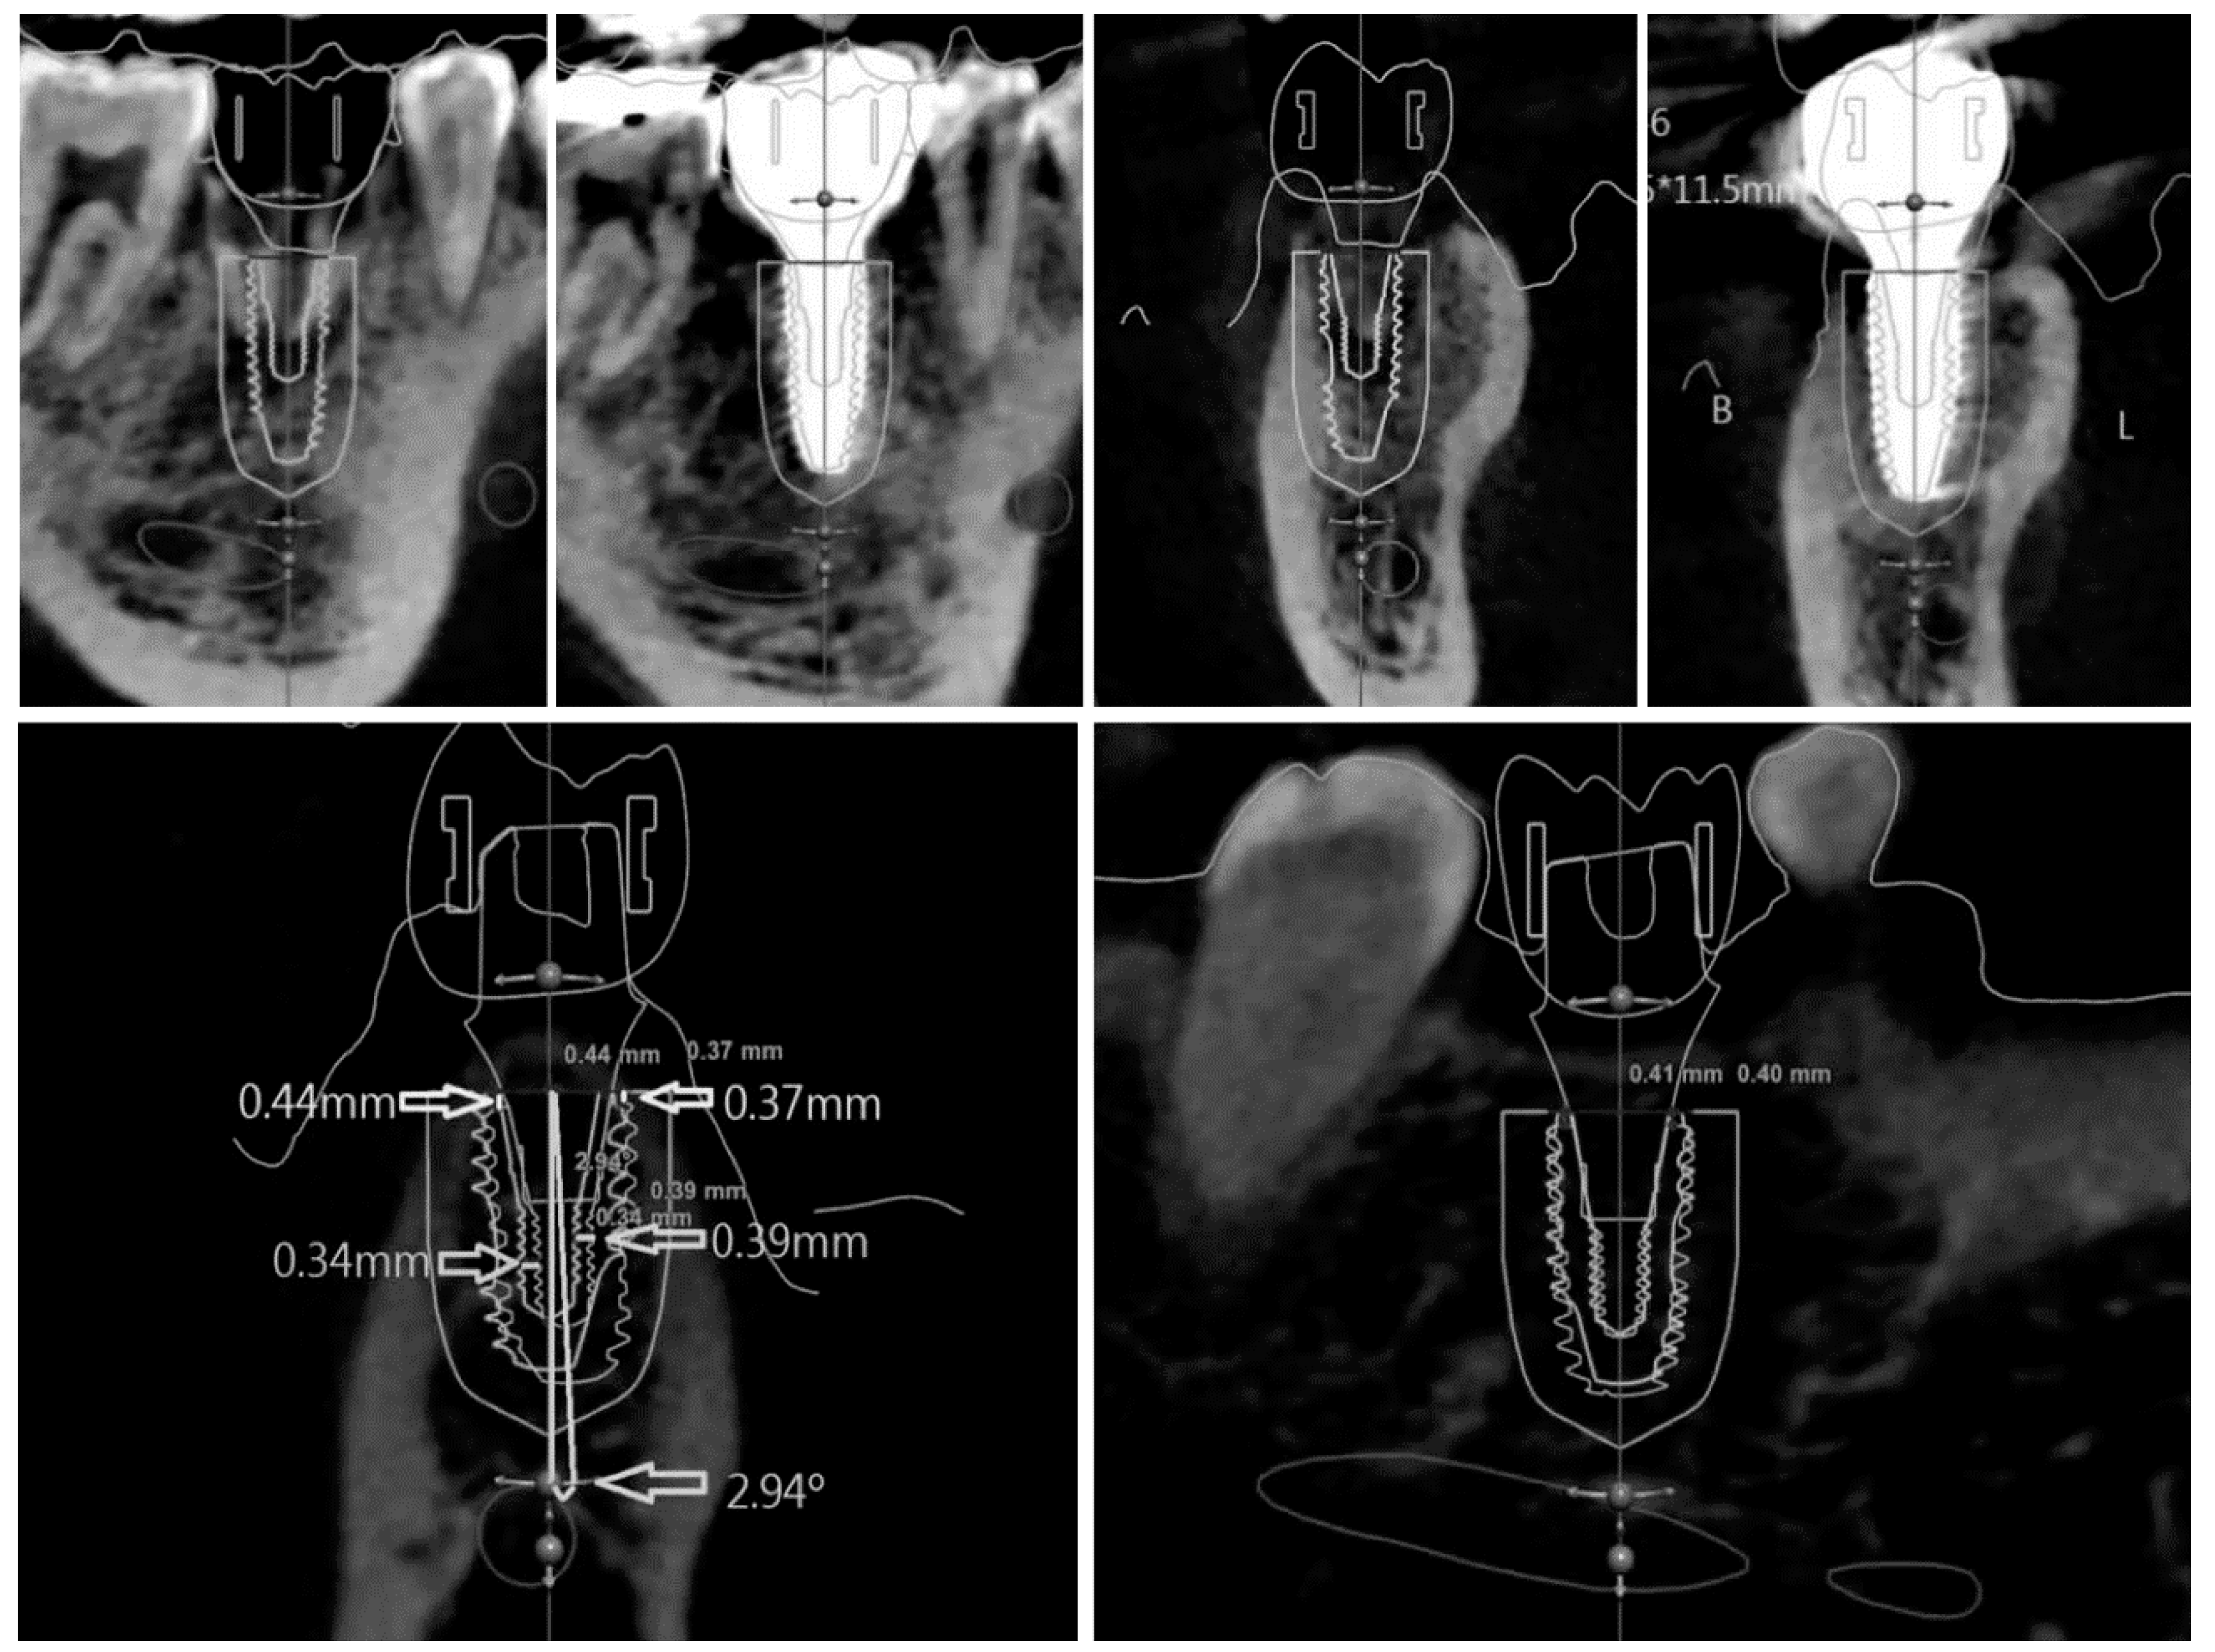

2.2.2. Scan Analysis

Instead of impression coping, an implant scan body can be used to determine the placed position with an intraoral scanner. In this case, a gypsum model is replaced with a digital model. This method indirectly confirms the position of the actual implant by matching the scan body outline and the virtual connecting of implant fixture. First of all, the position of the scan body should be completely matched in both the library file and the intraoral scan data. As this procedure is performed manually, however, the implant position can be altered significantly, even with a minimal error. Once the location of the scan body is determined, the implant position can be identified by a library image that virtually combines the implant fixture and scan body. Figure 4 shows the results of comparing the preoperative and postoperative scan copings on the patients who received implant guide surgery at Seoul National University Dental Hospital. Intraoral scanner (Trios3®, 3 Shape, Copenhagen, Denmark) and Implant studio™ (3 Shape, Copenhagen, Denmark) were used for analysis (Figure 4). It is also possible to compare it with the surrounding anatomical structure by superimposing the CT data before surgery. The indirect method (impression taking) has an additional step of connecting and removing the impression coping or scan body, therefore the possibility of an error is inevitable. In 2013, Platzer et al. [11] sandblasted a healing abutment that was designed to prevent rotation in pre-operative and post-operative implant, and connected it with 25 Ncm force, using the abutment as a scan body by digitizing it with a laser scanner. In the author’s opinion, it can be better to use a fixture mounter when placing an implant and obtaining the implant’s position information by intraoral scanner using the mounter as the scan body. This technique would be able to reduce the error.

In a similar way, as the actual placed position of implant in Figure 6 was confirmed by the “scan analysis method” using the principle of impression taking, the planned position was loaded by the scan image (Figure 6). The reference point and the background data for comparison are all in the scan data. Consequently, the accuracy of the superposition is determined by the resolution of the intraoral scanner, which consists of a STL file.

Figure 6. Displacement measurement by indirect method. The planned position (purple) and the placed position (red) are superimposed.